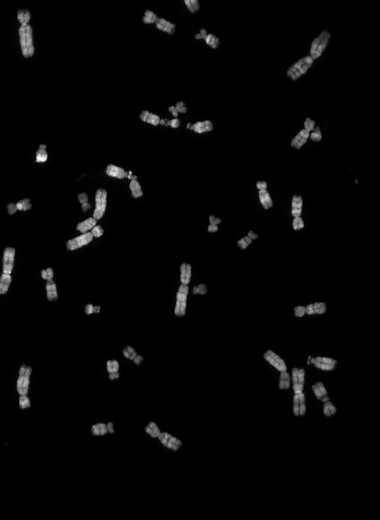

Из чего же сделаны наши мальчишки и девчонки Из чего же сделаны наши мальчишки и девчонки

Что именно мы наследуем от мамы, а что — от папы?